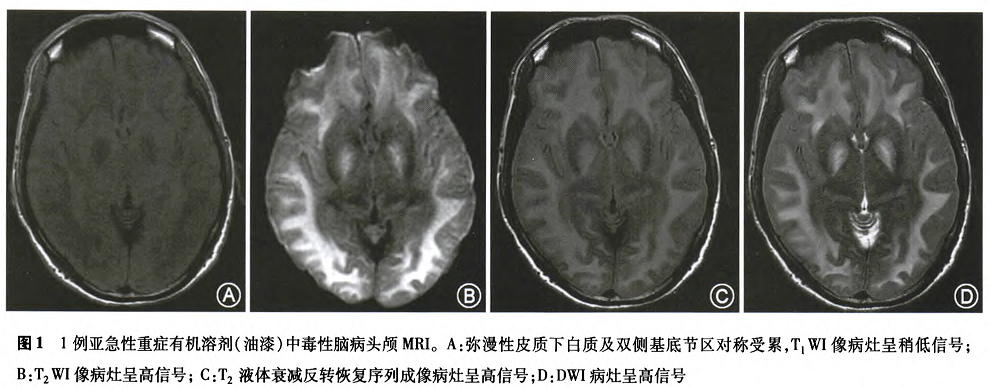

MRI在有机溶剂中毒性脑病的诊断上具重要价值。急性和亚急性有机溶剂中毒性脑病的患者在MRI上以双侧对称性或弥漫性白质、基底节区、齿状核受累为主,有的患者可累及小脑白质和脑干,重症患者可以表现为全脑肿胀、广泛对称的白质疏松水肿、灰白质分界不清,随着患者临床症状的好转,上述影像学损害可以部分或完全恢复。图1是我科收治的1例油漆中毒性白质脑病头颅MRI影像,可见弥漫性脑白质及基底节异常信号。